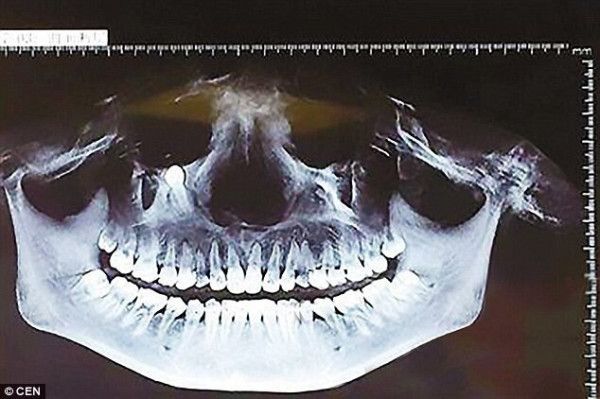

의사쌤 : 사랑니가 눈 쪽에 있는데요?.jpg